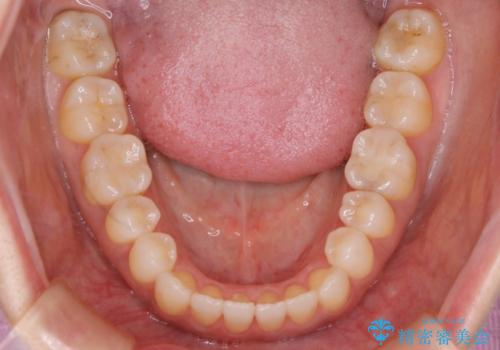

【非抜歯】短期間で実現する前歯の反対咬合治療

- 前歯のガタつきを主訴に来院されました。

奥歯の噛み合わせにはほとんど問題が見られず、歯列拡大とIPRのみの必要最低限の移動で歯並びの治療を計画することとなりました。

拡大とIPR

歯列の幅を拡大することにより作れるスペースは想像より大きく、実際に拡大だけでガタつきが治せるというケースもあります。

その他の歯のガタつきをとるためのスペース作りの方法の一つにディスキング(IPR)という方法があります。

歯と歯の間を一ケ所あたり最大0.5mmまでの範囲内で削ることで歯自体が少し小さくなり、それにより作られるスペースを数ヶ所分合わせることで合計で数mmの大きなスペースが作れるという方法です。